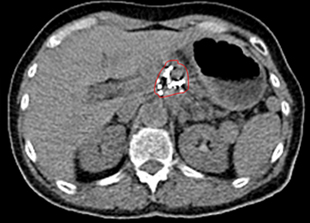

比瑞特的CT图示治疗前胰腺头体部巨大肿瘤,活捡腺癌;

治疗后10个月复查CT,显示病变显著缩小,PET上无活性,提示肿瘤坏死